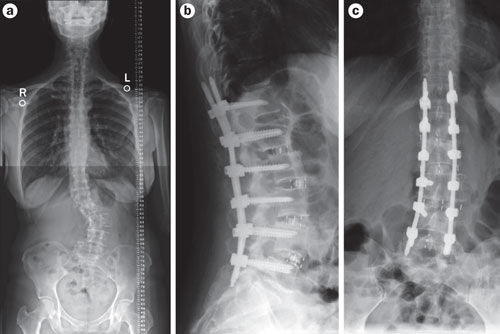

Low back pain refers to pain that you feel in your lower back. You may also have back stiffness, decreased movement of the lower back, and difficulty standing straight. Low back pain that is long-term is called chronic low back pain.

Many people with chronic back pain have arthritis. Or they may have extra wear and tear of the spine, which may be due to:

You may have had a herniated disk, in which part of the spinal disk pushed onto nearby nerves. Normally, the disks provide space and cushion in your spine. If these disks dry out and become thinner and more brittle, you can lose movement in the spine over time.